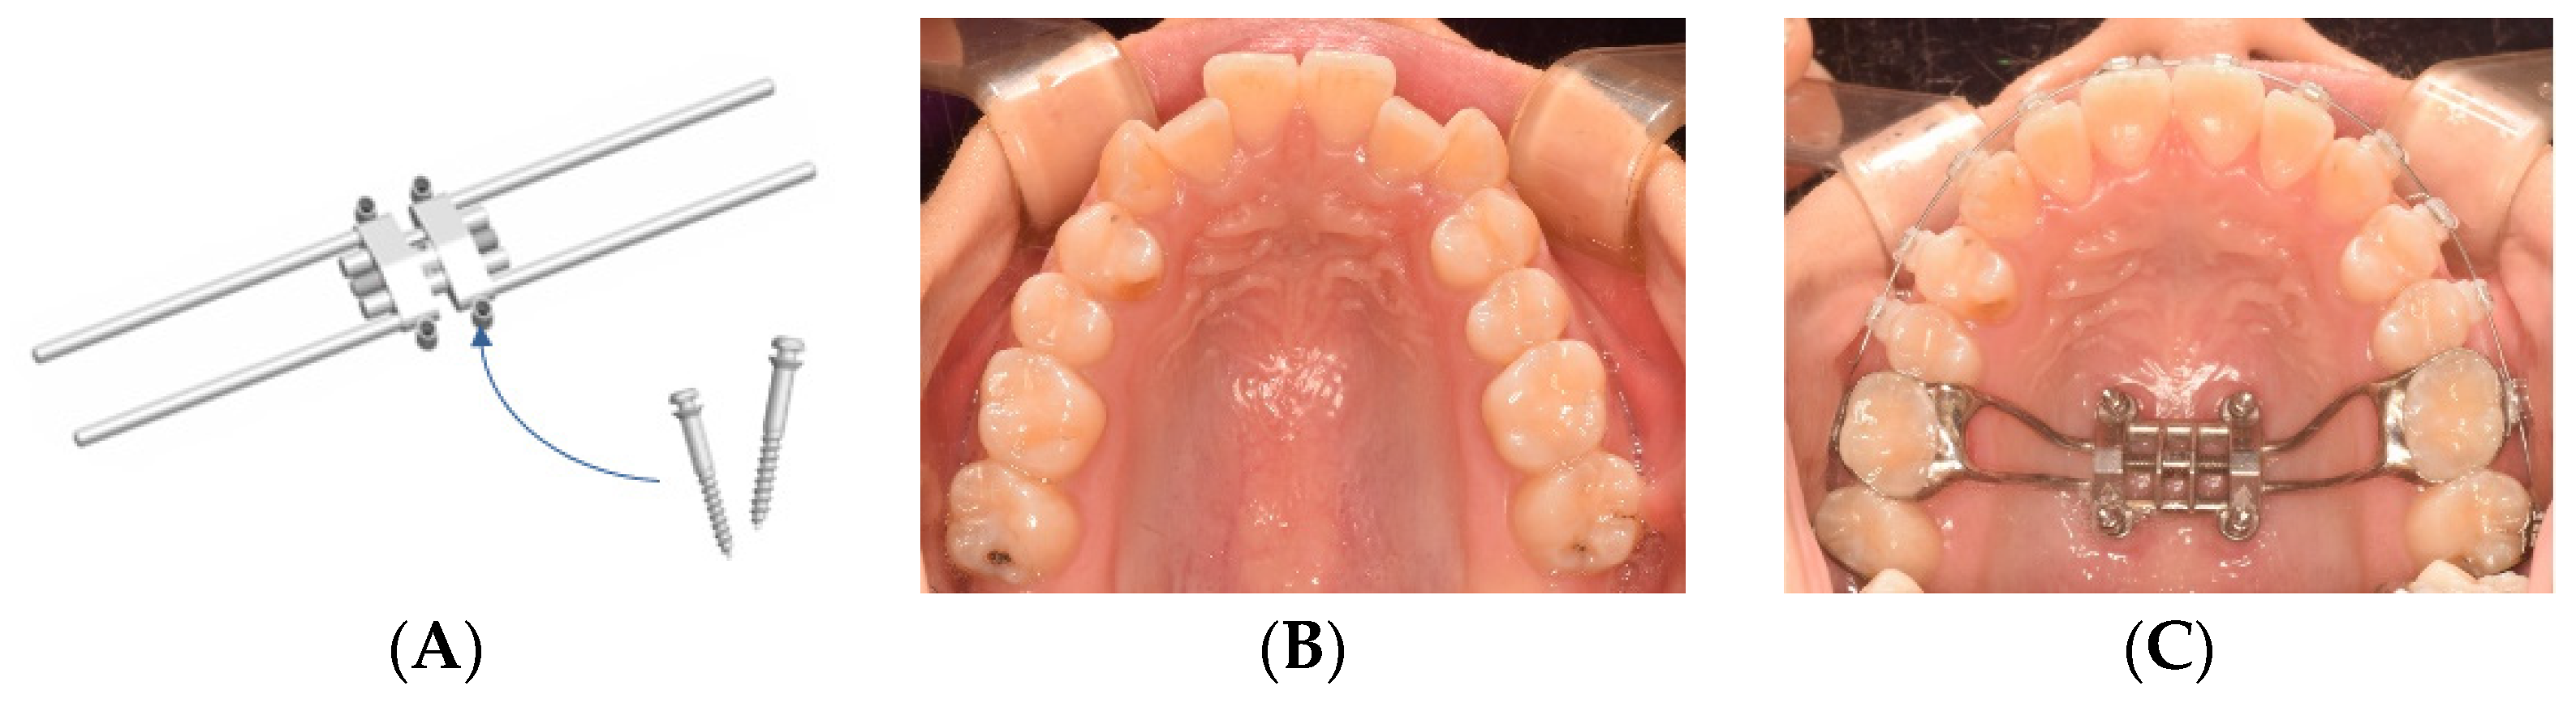

2.2. Materials and Treatment Protocol